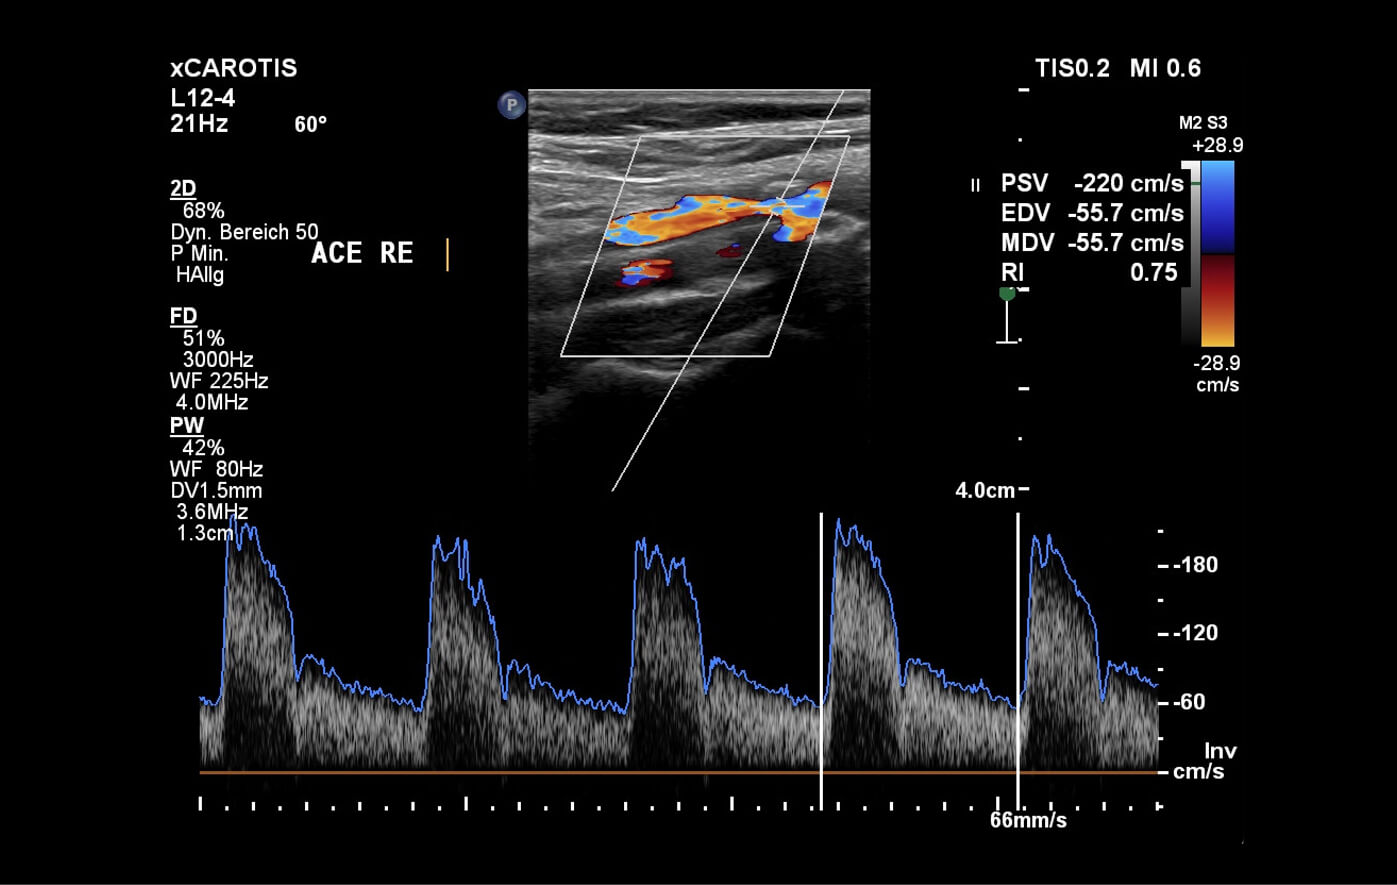

Die Duplexsonographie der Halsgefäße ist eine Ultraschalluntersuchung, mit der wir die Blutgefäße am Hals, insbesondere die Halsschlagadern, beurteilen. Dabei können wir Ablagerungen (Plaques) oder Verengungen (Stenosen) frühzeitig erkennen, die das Risiko für einen Schlaganfall erhöhen können. Die Untersuchung dauert nur wenige Minuten und liefert wichtige Informationen über die Durchblutung Ihres Gehirns und das Ausmaß der Gefäßveränderungen (Atherosklerose).